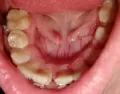

Хотела пройти процедуру чистки зубов, до этого носила брекеты, остались после них пятна. На тех местах, где ставили пломбы, образовались желто-коричневые пятна. Когда пришла к врачу, тот сказал, что чистка не поможет, нужно только спиливать те участки, где пятна и пломбировать.

Неужели другого выхода нет и ультразвуковая чистка бессильна?

Ультразвуковая чистка вообще противопоказана для чистки налета, данная манипуляция предназначена для удаления зубного камня и только. Для чистки налета необходимо пройти процедуру Айр-Фло. Но и это скорее вас не спасет. Скорее поражение слишком глубоко и придется препарировать пломбы.